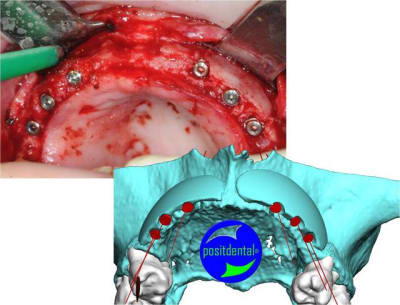

je peux enfin confirmer que la greffe biobank, autorise l'expansion en deuxième intention.

même si je n'ai pas fait un super bombé vestibulaire je me suis permis de faire un mini expansion de crête en particulier sur 22

Faisons un peu de prospective, je joins la photo 3D réalisé y a plusieur mois montrant ce qui est espéré et la photo que tu à mis en ligne sur eugenol, chacun sera en mesure de jugé de la qualité du résultat obtenu.

> Faisons un peu de prospective, je joins la photo 3D réalisé y a plusieurs mois

> montrant ce qui est espéré et la photo que tu à mis en ligne sur eugénol, chacun

> sera en mesure de jugé de la qualité du résultat obtenu.